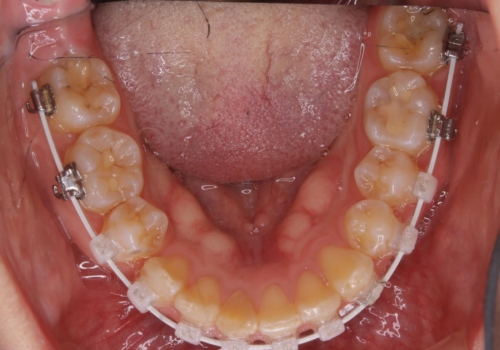

- ワイヤー矯正 審美装置

また、右下の歯が生まれつき少なく、隙間が空いている状態でした。

矯正治療でご自身の歯を移動して閉じることにしました。

また、咬んだときに下の前歯が隠れる過蓋咬合でしたが、矯正治療で改善しました。